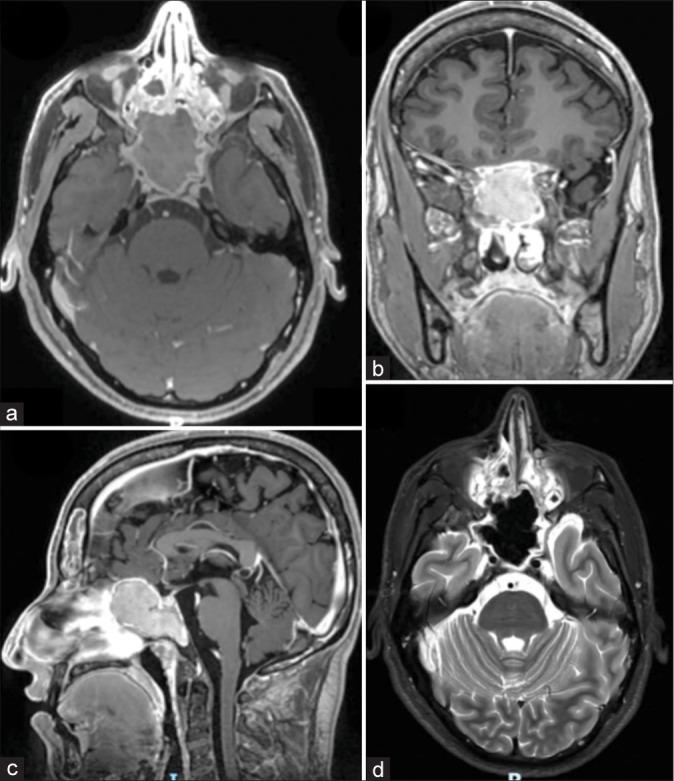

Fungal infections should always be considered in difficult-to-treat paranasal sinus conditions. Sphenoid fungal balls are characterized by the presence of dense fungal masses in the sinus cavity without invasion of surrounding tissues. This case emphasizes the importance of accurate terminology and management and also highlights the involvement of rare pathogens such as . Diagnosis is typically based on imaging studies and intraoperative findings. Accurate identification of the pathogen is crucial. Fungal infections of the paranasal sinuses, including fungus balls, can present challenges in diagnosis and treatment. , although infrequent, can cause potential life-threatening infections.

CASE DESCRIPTION

We present a 26-year-old non-HIV male patient who presented with nasal symptoms and mild headaches. The patient underwent an endoscopic exploration that revealed a soft, grayish lesion with a buttery consistency. Gross total resection was achieved and the lesion was identified as being caused by ; thus, intravenous antifungal treatment was given.

在难以治疗的鼻窦疾病中应始终考虑真菌感染。蝶窦真菌球的特征是鼻窦腔内存在致密的真菌团块,而不侵犯周围组织。本病例强调了准确的术语和管理的重要性,也突出了罕见病原体如……的参与。诊断通常基于影像学研究和术中发现。准确识别病原体至关重要。鼻窦真菌感染,包括真菌球,在诊断和治疗方面可能会带来挑战。……虽然不常见,但可导致潜在的危及生命的感染。

病例描述

我们报告一名26岁非HIV男性患者,出现鼻部症状和轻度头痛。患者接受了内镜探查,发现一个质地柔软、呈灰色、具有黄油样质地的病变。实现了全切除,病变被确定为由……引起;因此,给予了静脉抗真菌治疗。